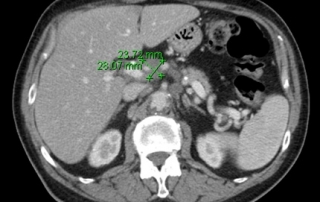

La biopsie guidée sous scanner de la masse mésentérique conduit au diagnostic de lymphome diffus à grandes cellules B CD20+ avec des zones évoquant la transformation d’un lymphome folliculaire en lymphome agressif.

Biologie : hémogramme normal, LDH augmentées à 720 UI. Biopsie médullaire et le myélogramme et l’immunophénotype médullaire montre une infiltration médullaire par un lymphome folliculaire à petites cellules, l’examen cytogénétique retrouve une translocation t(14 ;18), et l’étude en biologie moléculaire un réarrangement du gène Bcl2.

Classement LNH diffus à grandes cellules CD20+ transformation d’un lymphome folliculaire, stade IV péritonéal et médullaire, OMS = 1, LDH augmentées. L’infiltration médullaire à petites cellules caractérise la transformation du lymphome folliculaire, et n’a pas la valeur pronostique péjorative d’une infiltration médullaire d’un lymphome à grandes cellules.

Décision Traitement initial par R-ACVBP x 4 cycles avec prophylaxie neuro-méningée. Recueil d’un greffon CSP après 4ème cycles. Consolidation par métothréxate à hautes doses et conditionnement BEAM autogreffe de cellules souches sous réserve d’obtention d’une réponse complète